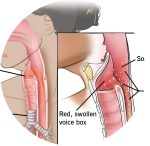

reflux.